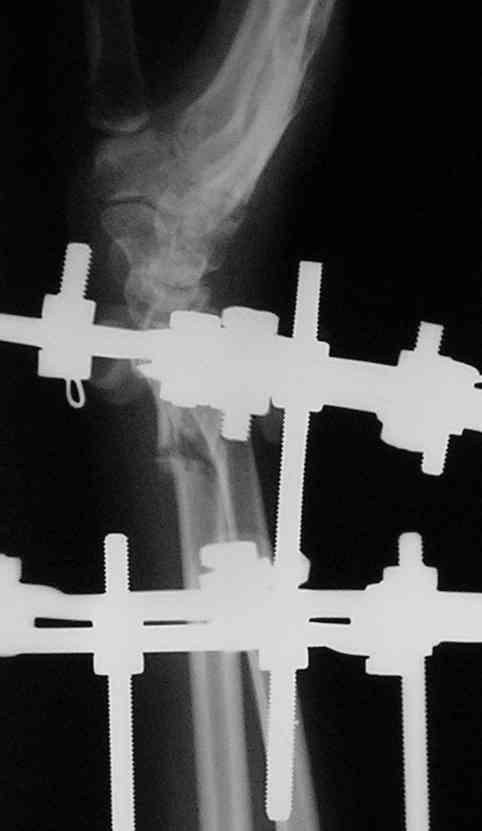

Спице-стержневой аппарат с компактотомией лучевой кости, костная пластика локтевой с удалением пластины. Не комфортно, но больше шансов на благоприятный исход. Заканчиваю лечение с похожей деформацией лучевой кости.